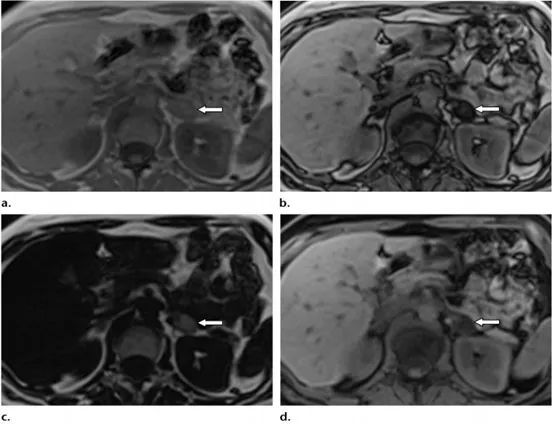

③肾上腺病变的鉴别诊断:肾上腺腺瘤是发生在肾上腺皮质最常见的肾上腺肿瘤,其肿瘤细胞含有大量细胞内脂质。典型表现是反相位图像上的均匀信号明显下降(图3)。其敏感性为70~80%,特异性可达90~95%。

图3:一例典型肾上腺腺瘤患者的CSI。与同相位图像a)相比,反相位图像b)中病变(箭头)的信号强度较低;病变在纯脂图c) 上具有高信号强度,在纯水图d) 上具有中低信号强度。